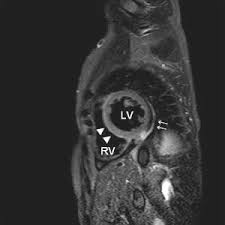

Inflammatory and endocrine causes picornavirus. Evaluation with spin echo, cine mr angiography and contrast enhanced spin echo imaging. Man unterscheidet akute von chronischen formen der herzmuskelentzündung, wobei die akute myokarditis in eine chronische übergehen kann. Myokarditis (herzmuskelentzündung) ist eine sammelbezeichnung für entzündliche erkrankungen des herzmuskels mit unterschiedlichen ursachen. Most of the time, it is caused by an infection that reaches the heart.

Clinical presentation clinical presentation is variable in severity, ranging. Myocarditis, also known as inflammatory cardiomyopathy, is inflammation of the heart muscle. Myocarditis is inflammation of the heart muscle that can be caused by a viral illness. Myocarditis is an uncommon disorder. Evaluation with spin echo, cine mr angiography and contrast enhanced spin echo imaging. Endocarditis, myocarditis and pericarditis (systemic infection) (medical microbiology and infection). Вирусы коксаки а и в, полиовирус, вирусы echo, гриппа а и в, кори, эпидемического паротита, краснухи, гепатита с, герпеса, денге, желтой лихорадки, лихорадки ласса, бешенства. Myocarditis echo features (page 1). Journal of the american college of cardiology vol. Most of the time, it is caused by an infection that reaches the heart. Adenovirus (a1, 2, 3, 5) larva migrans. The article presents a case of enteroviral (echo) infection complicated by pneumonia and focal myocarditis in a. ▪ герпес вирус 6 типа.

Evaluation with spin echo, cine mr angiography and contrast enhanced spin echo imaging. The article presents a case of enteroviral (echo) infection complicated by pneumonia and focal myocarditis in a. Adenovirus (a1, 2, 3, 5) larva migrans. Echo viruses cause the disease mostly in childhood. Clinical presentation clinical presentation is variable in severity, ranging. Day 1 or the first echocardiographic study, day 5, day 7. Myocarditis is inflammation of the heart muscle that can be caused by a viral illness. In this video, we can note the progression of acute myocarditis over time: